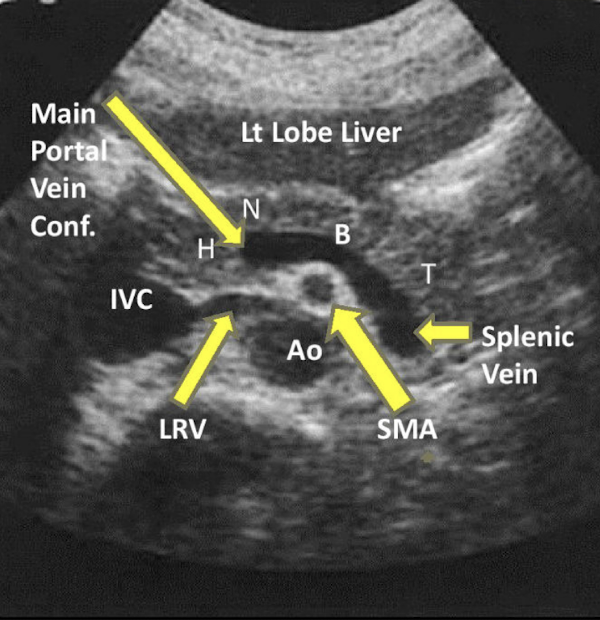

Be able to identify this image taken in a transverse plane

label this image

label

identify all structures

A) left liver lobe

B) gastroduodenal artery

C) common bile duct

D) Main portal confluence

E) Splenic vein

F) SMA

G) IVC

H) Aorta